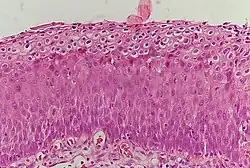

CIN 3 (Grade III)

• Severe dysplasia with undifferentiated neoplastic cells that span more than 2/3 of the epithelium

• May involve the full thickness

• May also be referred to as cervical carcinoma in situ

• CIN 3+ encompasses CIN 3, AIS, and cancer